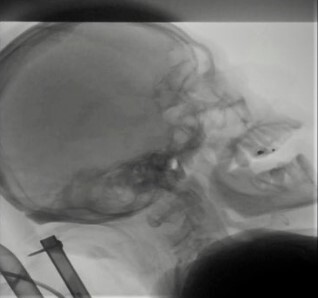

嚥下造影検査

レントゲン透視下で造影剤入りの食べ物を摂ってもらうことで、飲み込みの状態を確認します。内視鏡とは違って,ノドの様子を直接見ることはできませんが、口から食道の入り口付近まで一連の飲み込みの動きを確認することができます。また内視鏡のような道具の挿入もないので違和感なく実施できるという利点があります。

レントゲンの動画で飲み込みを確認します。